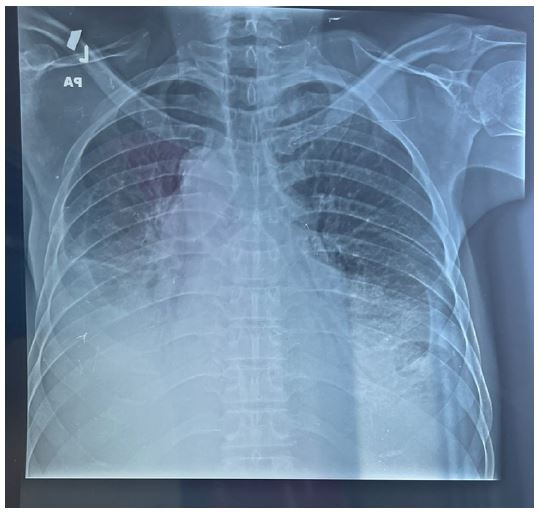

Figure 6: Showing associated bilateral moderate pleural effusion with lung atelectasis.

Figure 7: Showing clear pleural space after thoracic drains placed with good lung re-expansion.